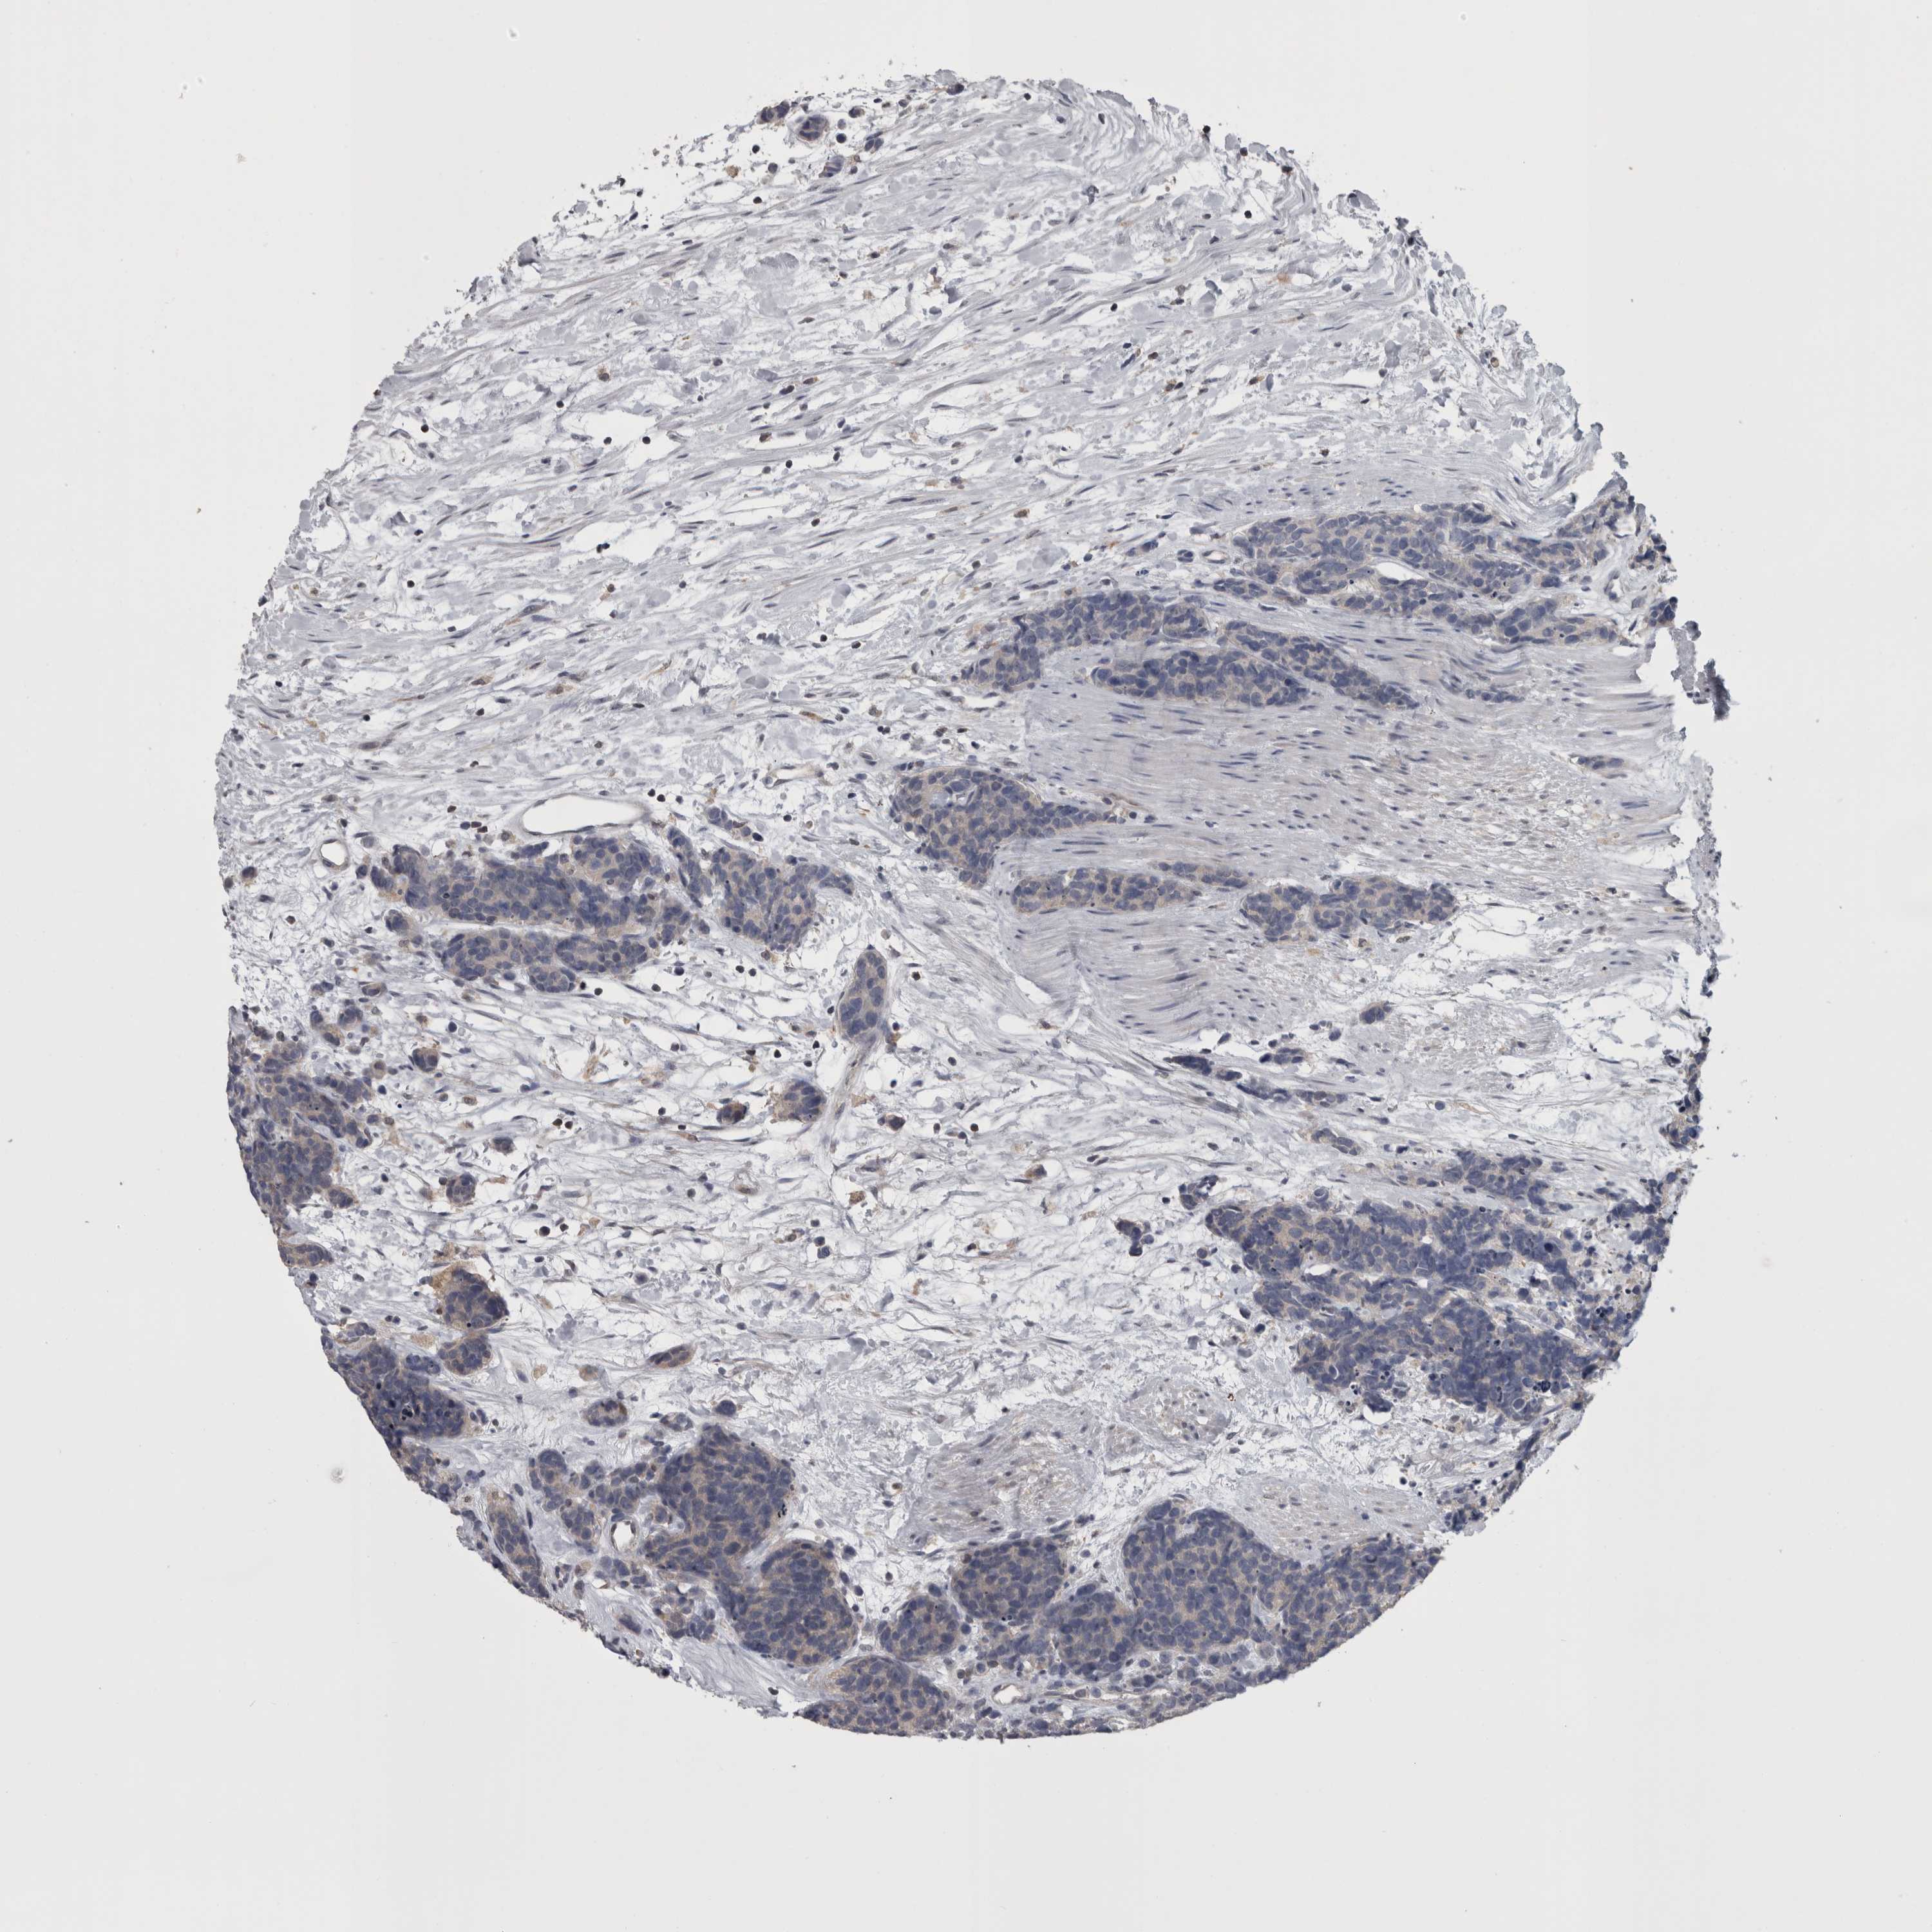

CARCINOID - Protein expressioni

A mouse-over function shows sample information and annotation data. Click on an image to view it in a full screen mode. Samples can be filtered based on level of antibody staining by selecting one or several of the following categories: high, medium, low and not detected. The assay and annotation is described here.

Each image is clickable and will lead to virtual microscopy that enables deeper exploration of all samples and also displays staining intensity scores, fraction scores and subcellular localization as well as patient and tissue information for each sample.

Antibody HPA026681

Staining

High

Medium

Low

Not detected

Intensity

Strong

Moderate

Weak

Negative

Quantity

>75%

75%-25%

<25%

None

Location

Nuclear

Cytoplasmic/membranous

Cytoplasmic/membranous,nuclear

Carcinoid, malignant, NOS

Carcinoma, NOS